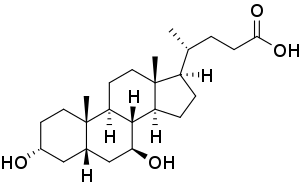

- In cholestatic liver disease, (where the flow of bile is affected due to cystic fibrosis[53]) a medication called ursodeoxycholic acid may be given.[54]